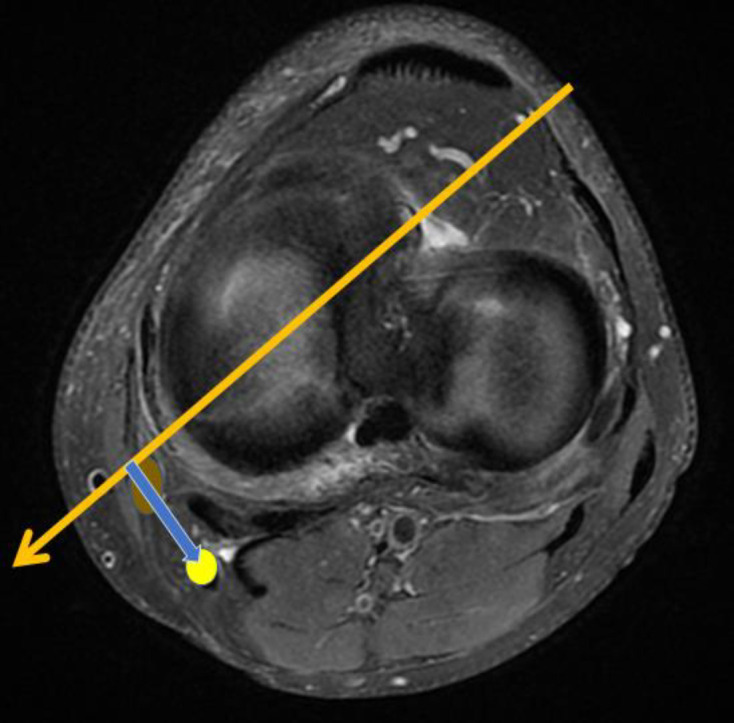

Objectives: This study investigates the risk of CPN injury by measuring the nerve's proximity to the trajectory of a straight needle inserted from the anteromedial portal at the knee joint level during inside-out lateral meniscus repairs in both ACL-injured and normal knees.

Methods: In this retrospective study, we examined MRI scans of 30 ACL-injured knees and 30 normal knees. A reference line was drawn 1 cm medial to the patellar tendon at the joint level, extending to the lateral margin of the popliteus and continuing posteriorly. Perpendicular distances from this line to the CPN were measured to compare anatomical variations between the groups. These measurements were analyzed using paired t-tests, with a p-value of less than 0.05, which is considered statistically significant.